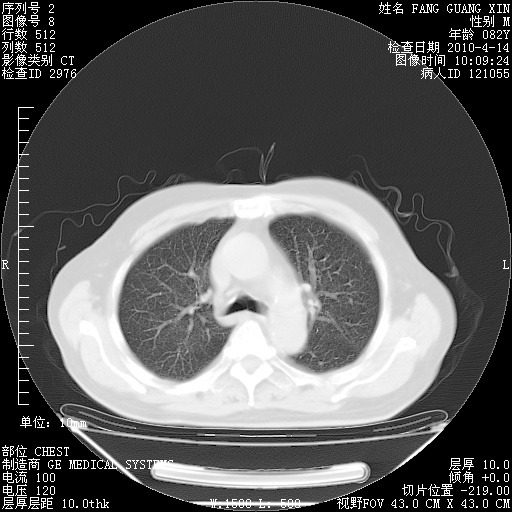

肺部CT平扫未见异常。